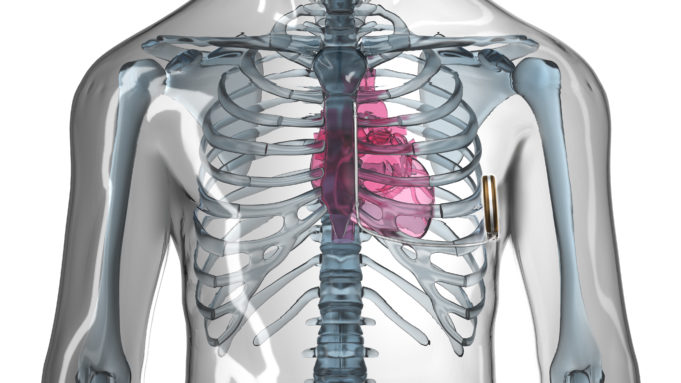

Boston Scientific has received US Food and Drug Administration (FDA) 510(k) clearance for the Lux-Dx insertable cardiac monitor (ICM) system, a new, long-term diagnostic device implanted in patients to detect arrhythmias associated with conditions such as atrial fibrillation (AF),...